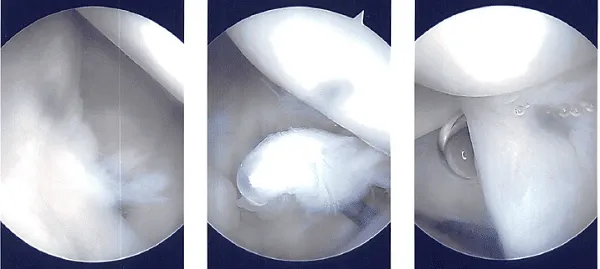

Un puff ocupaba la posición, y todas las protuberancias óseas estaban bien acolchadas. Detrás de la esquina posterolateral del acromión se realizó una incisión quirúrgica. La articulación glenohumeral fue penetrada con el endoscopio. Hubo un examen conjunto glenohumeral.

El agujero del labrum estaba presente. Las degeneraciones labrales se eliminaban afeitando. El labrum posterior presentaba degeneración, que se limpiaba afeitando. Había bursitis subacromial.

Con una afeitadora, se realizó una bursectomía exhaustiva. Se creó un portal lateral. El acromion estaba deshilachado y tenía una configuración tipo 2 (configuración curva).

Se decidió hacer acromioplastia. Tras limpiar con una varita térmica y una fresa, se realizó una acromioplastia. La articulación AC fue revisada tras una acromioplastia completa y se encontró degeneración. Se planeó la excisión de la clavícula distal. La clavícula distal se extrajo con una varita y luego una fresa.